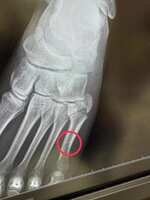

原來裂在這...

這應該是翻船才會那邊出力

演唱會後可能因為不確定傷的位置包得比較大,還好診斷後主要在左腳趾的位置,不是脛骨之類的

: 看有傷過同樣位置的粉絲說,當下真的會有骨頭啪嘰(?)的感覺,然後就會開始爆痛,不過分享的粉絲說他當時檢查裂的程度沒有Taka那麼大,所以體感上Taka的可能更痛…